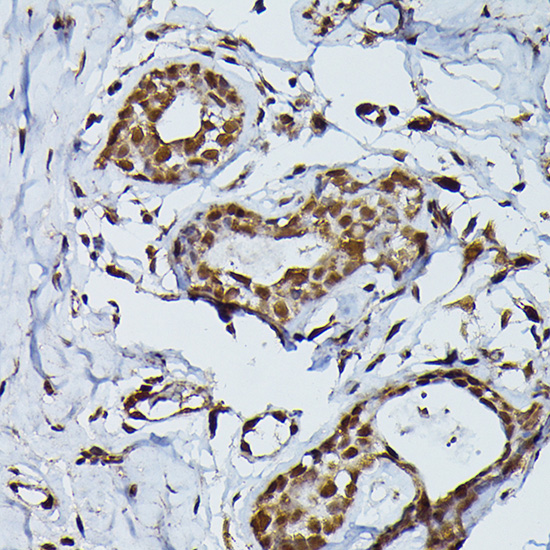

Immunohistochemistry of paraffin-embedded human breast cancer using PRPF4 Rabbit pAb.